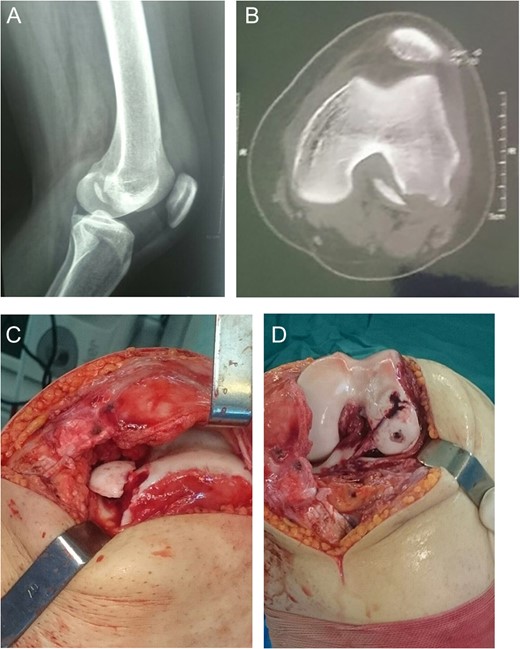

A 16-year-old female came with a history of falling down and knee twisting at the bathroom. She complained that her knee got deformed and reduced immediately on the field. Radiography showed a displaced OCF in the weight-bearing portion of the lateral femoral condyle [Fig.3A]. CT scan showed displaced femoral OCF and lateral patella subluxation [Fig. 3B]. With lateral parapatellar knee arthrotomy, the femoral OCF was reduced and fixed with bio-absorbable screws [Fig. 3C and D]. Her condition has not been followed up since then.

Case 3. A, Radiography showing lateral femoral condyle OCF. B, CT scan showing OCF and lateral patellar subluxation. C and D, Intraoperative photography showing weight-bearing position of OCF and fixation with bioscrews.